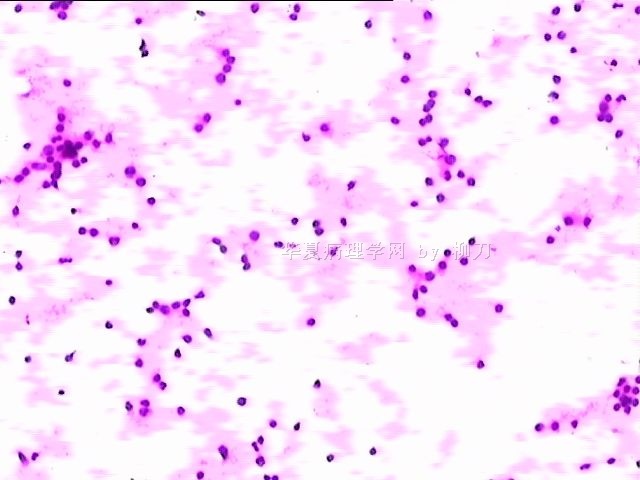

78y,男,胸水。 大家看看那些小于淋巴细胞的东东。

孢子?

图6感觉象是污染的孢子之类的东西。好好回忆一下,制片过程?容器?有没有污染的 可能?

像是孢子

同意孢子